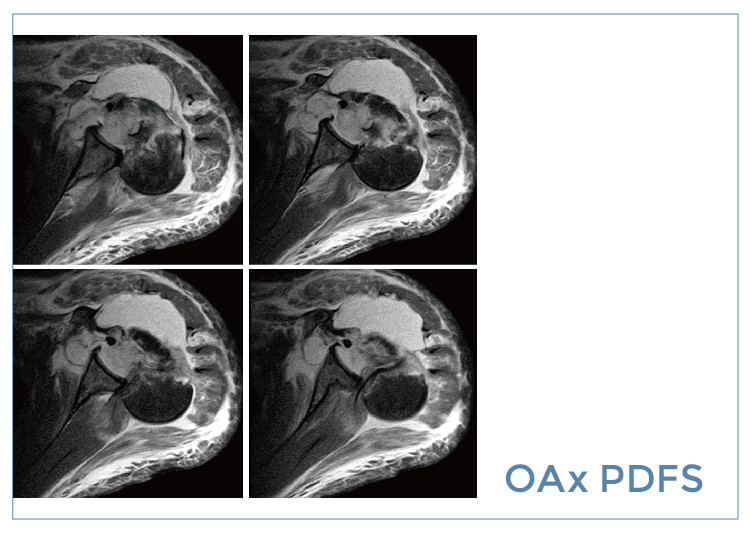

【朗润影像档案】20190830磁共振影像病例结果讨论